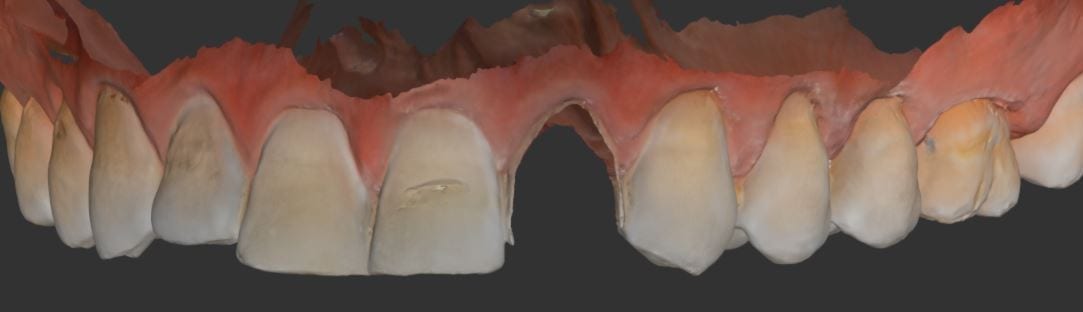

This article documents how to capture upper and lower scans for an oral appliance to treat obstructive sleep apnea. The patient was recently diagnosed with mild sleep apnea with a […]

This is a case imaged for an occlusal guard, wehre the upper arch took only 43 seconds to capture. Afterwads, the lower arch is captured, and then ultimately we move […]